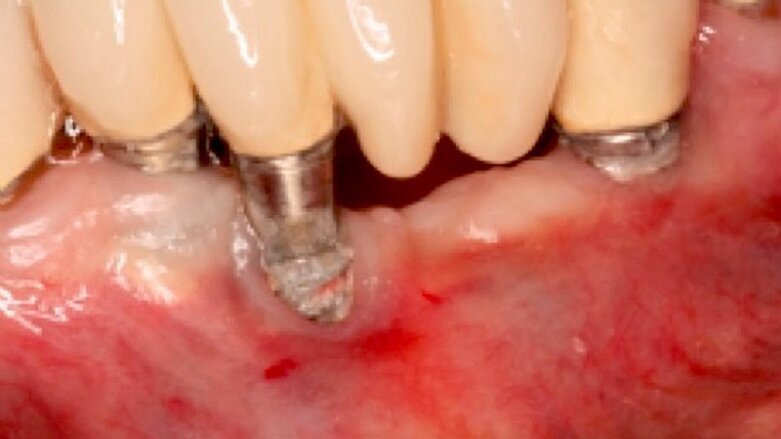

En el caso que nos ocupa, evaluamos con cortes de tomografía Cone Beam (CBCT) la regeneración ósea que se realiza en un implante, utilizando el siguiente procedimiento:

- Utilizamos en el implante con peri-implantitis un láser de erbio cromo YSSG de longitud de onda 2.780 nm para descontaminar la superficie del implante y su alrededor.

- Después utilizamos un láser de diodo de longitud de onda de 940 Nm para estimular la regeneración ósea.

El resultado obtenido en el tiempo de la aplicación del láser es un incremento observable de la densidad ósea. En cuando a los parámetros utilizados en la tomografía Cone Beam, se trata del mismo corte en las cuatro imágenes con el fin de obtener cálculos precisos.

Fig 2. Tomografía inicial. En distal del implante se observa un halo hipodenso desde el reborde, que se dirige a la parte apical, lo que es compatible con peri-implantitis; a nivel del reborde óseo mesial y distal observamos pérdida ósea. Como indican las flechas, se realiza una descontaminación con láser de erbio cromo YSSG alrededor del implante que remueve todo microorganismo.